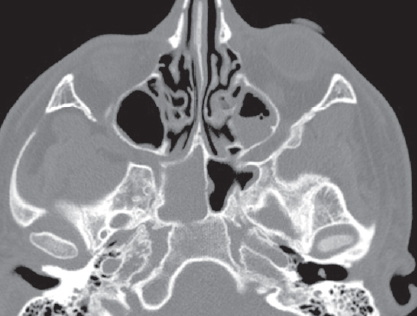

Риногенные внутричерепные осложнения, такие как абсцесс головного мозга и тромбоз вен и синусов головного мозга, по сей день остаются грозной, жизнеугрожающей патологией, не редко заканчивающейся летальным исходом, несмотря на широкое развитие антибактериальной терапии и приверженность пациентов к проводимому лечению. Нередко причиной развития внутричерепных осложнений служит обострение хронического воспалительного процесса в придаточных пазухах носа, тогда как острая ЛОР-патология синусов приводит к развитию риногенных осложнений лишь в небольшом проценте случаев. К сожалению, высокое развитие лучевой и лабораторной диагностики не всегда позволяет вовремя диагностировать данные состояния и оказать адекватную хирургическую помощь. В детском и подростковом возрасте важно выполнить своевременное полное и в то же время малоинвазивное, не приводящее к инвалидизации, хирургическое пособие. Анализ зарубежной литературы последних лет показывает, что нейрохирургические операции в различном объеме (от трепанопункции головного мозга до краниотомии) встречаются в подавляющем большинстве случаев лечения риногенных внутричерепных осложнений. В статье приводятся два клинических случая успешно пролеченных в отделении оториноларингологии Санкт-Петербургского государственного педиатрического медицинского университета пациентов с внутричерепными осложнениями без высокотравматичной нейрохирургической операции. Комбинация эндоназальной эндоскопической операции и массивной адекватной консервативной терапии (антибиотикотерапия в сочетании с применением антикоагулянтов при синус-тромбозе) позволяет добиться выздоровления пациента без обращения к нейрохирургическому вмешательству.